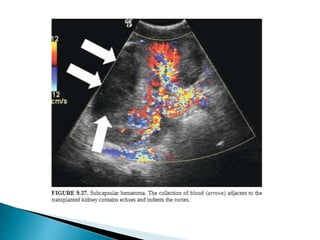

 Unusual complication.

 First 2 weeks of transplant surgery.

 Predisposing causes :- Acute rejection. ATN, vascular occlusion.

 Imaging

1. Renal parenchymal laceration

2. Intra-renal hematoma

3. Peri-renal hematoma.

1. USG:- hypoechoic fluid collection represents a hematoma within the

laceration/peri-nephric space.

2. CT:- dense clot within the laceration/peri-nephric space.